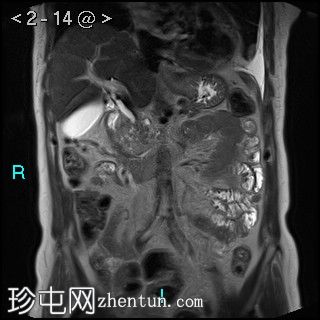

轴位

弥散加权成像 (DWI)

胰腺钩突附近可见边界不清的肿块,T2加权像呈不均匀中等信号,弥散受限明显。肿块大小为4.1 x 5 x 3 cm(前后径 x 横径 x 头尾径)。伴有胰管扩张,直径约6 mm。

肝脏可见多个大小不一的可疑病灶(从亚厘米级到2厘米不等)。T2加权像呈高信号,弥散受限明显。

远端胆总管突然变窄,但未完全阻塞。

胰腺周围可见多发囊性病变,部分与主胰管相连,提示胰腺导管内乳头状黏液性肿瘤(IPMN)。

双侧胸腔积液,左侧较多。